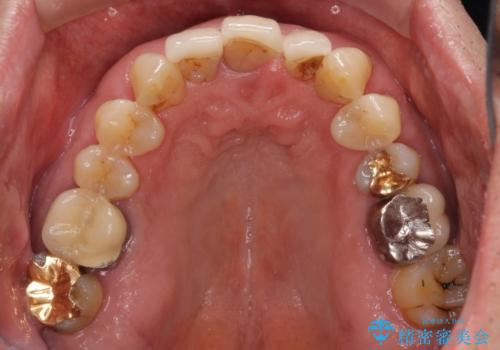

- 上の前歯が痛むとのことで来院された患者様です。

検査を行ったところ、前歯1本は周辺の骨が失われており、抜歯が必要でした。

上顎の奥歯は全体的に歯周ポケットが散見され出血が認められたため、歯周外科処置を行うこととしました。

上の歯は見た目を良くしたいというご希望があったため、歯周外科処置を行った歯についてはセラミッククラウンで補綴することとしました。

また、前歯の部分矯正も希望されたため、歯周外科処置と平行して矯正治療を行うこととしました。